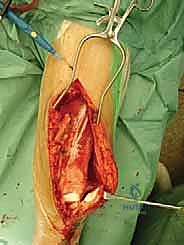

Exposure and Oncologic Resection

The incision is meticulously planned to incorporate the previous biopsy tract within an ellipse of skin, ensuring the tract is excised en bloc with the main tumor specimen to prevent local seeding. For a distal femoral resection, an extended anteromedial incision is utilized. Deep dissection proceeds through the virgin tissue planes, maintaining a thick cuff of normal muscle around the pseudocapsule of the tumor.

The neurovascular bundle (femoral/popliteal vessels) is identified proximally in the normal anatomy of the adductor canal and traced distally, carefully dissecting it away from the posterior aspect of the tumor block. Once the neurovascular structures are safeguarded and the joint capsule is appropriately addressed (often requiring intra-articular resection for distal femur, or extra-articular resection if the joint is contaminated), the level of the diaphyseal osteotomy is identified based on preoperative MRI measurements.

The osteotomy is performed using an oscillating saw under continuous saline irrigation to prevent thermal necrosis of the remaining bone. The entire tumor specimen is then delivered from the field and immediately sent for pathological evaluation of the margins.

The final, and arguably most crucial, step for functional recovery is the soft tissue reconstruction. The extensor mechanism must be meticulously reapproximated. In cases where significant local muscle was resected to achieve oncologic margins, rotational muscle flaps (such as a medial gastrocnemius flap for the proximal tibia) are frequently employed to provide robust, vascularized soft tissue coverage over the metallic implant, drastically reducing the risk of postoperative wound breakdown and deep infection.